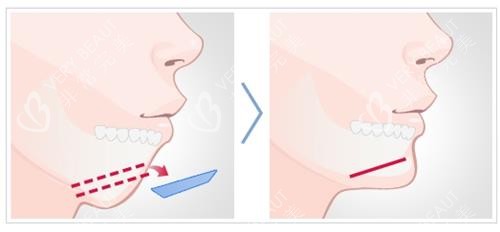

面诊那天,罗医生拿CT片给我看:“你的下颌骨过度前突,单纯正畸结果有限,双颚手术调整上下颌骨位置,才能根本解决问题。”他说话很慢,每个术语都用“下巴往前跑”“牙齿咬不齐”这种我能听懂的词解释,诊室墙上挂着2018年的患者术后对比照,现在还能找到那位姐姐的小红书账号——这让我踏实了。

醒来时在病房,下巴裹着弹力绷带,护士说“血压心率都稳”。前3天只能喝小米粥,脸肿得像“发面馒头”,但罗医生查房时说:“你的肿胀在预期范围内,说明组织反应正常。”第4天拆了部分绷带,能对着镜子看到下巴线条变平了,虽然还肿,但终于不是“月亮尖”了!

术后1周拆线,罗医生用棉签轻压伤口:“愈合得比较好,没感染。”回家后每天用漱口水清洁口腔,2周能吃软面条,1个月啃苹果,3个月朋友见我都问“你是不是瘦了?”——其实是下颌线出来了,脸看着小了一圈。